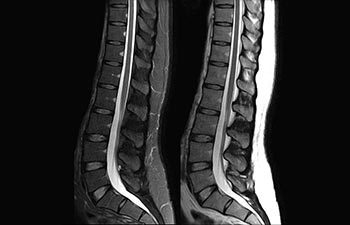

Sehen Sie selbst, was die ersten Nutzer von Ingenia Prodiva 1.5T über ihre Erfahrungen mit dem System und dessen Auswirkung auf ihre radiologische Praxis berichten.

Die richtige Geschwindigkeit bei jeder Untersuchung.